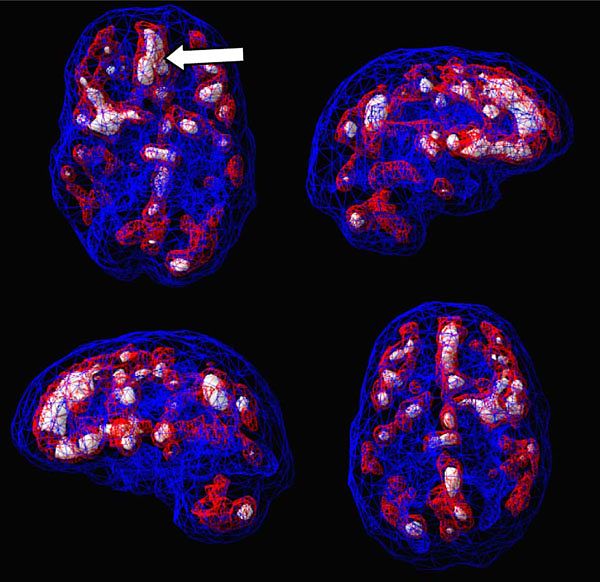

Active scan of an inmate who experienced trauma: state of decreased cerebral blood flow in the prefrontal cortex, which affects a person's personality, cognition, and rationality.

Brain imaging suggests that abnormalities in the brain can underlie acts of violence